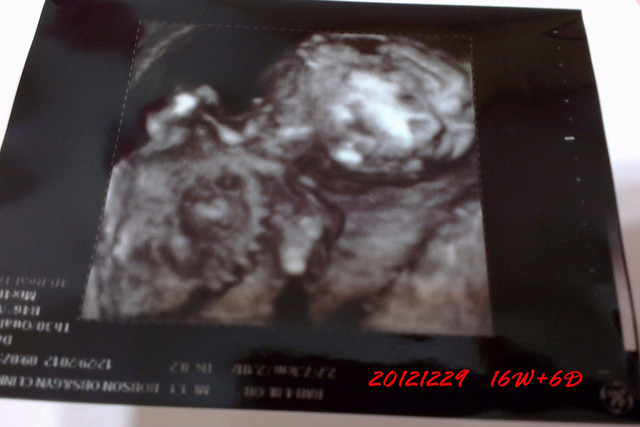

20121201去產檢的時候,發現小章魚已經成形囉

整個身體和頭都發展得很好

已經出現人的形狀了

感覺好特別

每天都在變化耶

而且這時已經滿3個月囉

終於過了安全期

而且這時的小章魚脊髓已經成形了

看看超音波照的好清楚

骨骼發育也很好